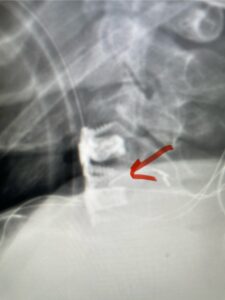

Fig. 4: Intraoperative lateral cervical x-ray demonstrating anterior cervical construct in good position at C 5 6 (red arrow)